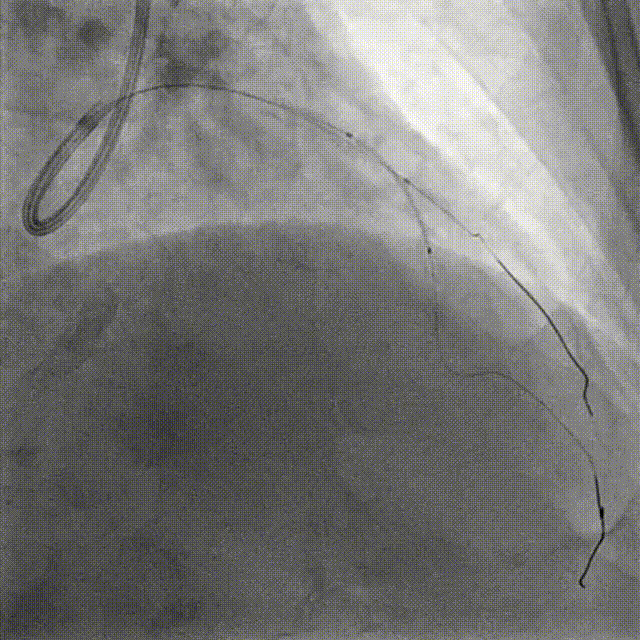

PCI-LAD TR, 7F EBU3.5

ROTA with 2.0mm burr

Angiography & Angioplasty NC 2.5*12mm